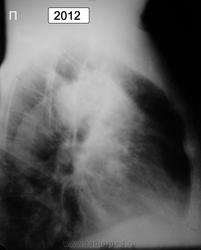

Ж.1938г.р. жалоб нет, более ранние рентг.описания - туберкулома

По-моему это типичный периферический рак

С уже "централизацией". Вопрос-больной наблюдается не мало-других мыслей кроме туберкуломы не было и он нигде больше не обследовался? Или это неизвестно?

был периферический кадато, стал централизоваться , пророс по бронхам как по рельсам :-)

должны были наблюдать в динамике , но характер тени уж совсем не за туберкулому!